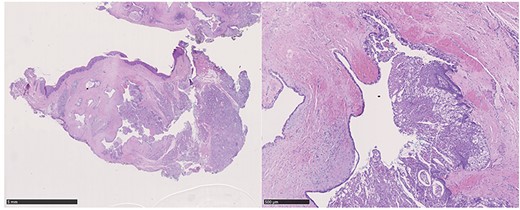

A 37-year-old patient with a recurrent, histologically confirmed steatocystoma of the palate was referred to our clinic. The patient’s medical history had already included two local removals of the tumor. Clinically, in the transition from hard to the soft palate, an asymptomatic, about 1 cm large, round, circumscribed and soft lesion was seen (Fig. 1). Magnetic resonance imaging was performed for further diagnosis and for assessment of spread and tissue infiltration of the finding. Here, a submucosal, 8 × 10 × 8 mm large tumor of delimited growth could be verified. It was T1 hypertense, T2 inhomogeneous partly hypointense, partly isointense with a significant signal drop in the T2 fat saturation (Fig. 2). There was no evidence of bony infiltration. The lesion was resected with a safety margin of 1–2 mm protecting the nerve and the greater palatine artery up to the palatal bone (Figs 3 and 4). As a secondary granulation of the defect was intended, the wound was first treated with a cellulose tamponade and tranexamic acid gel to prevent bleeding. An acrylic splint was then incorporated as a pressure bandage and wound protection (Fig. 5). The histopathological examination of the removed specimen showed a soft and glandular tissue covered with squamous epithelium with manifestations of a cystic, regressively changed epithelial lesion, which was compatible with the clinically known steatocystoma (Fig. 6). Follow-up examinations at 3-month intervals showed a good wound healing with complete restitution without evidence of recurrence after 1.5 years.

Hematoxylin–eosin staining: glandular tissue covered with squamous epithelium with manifestations of a cystic, regressively changed epithelial lesion